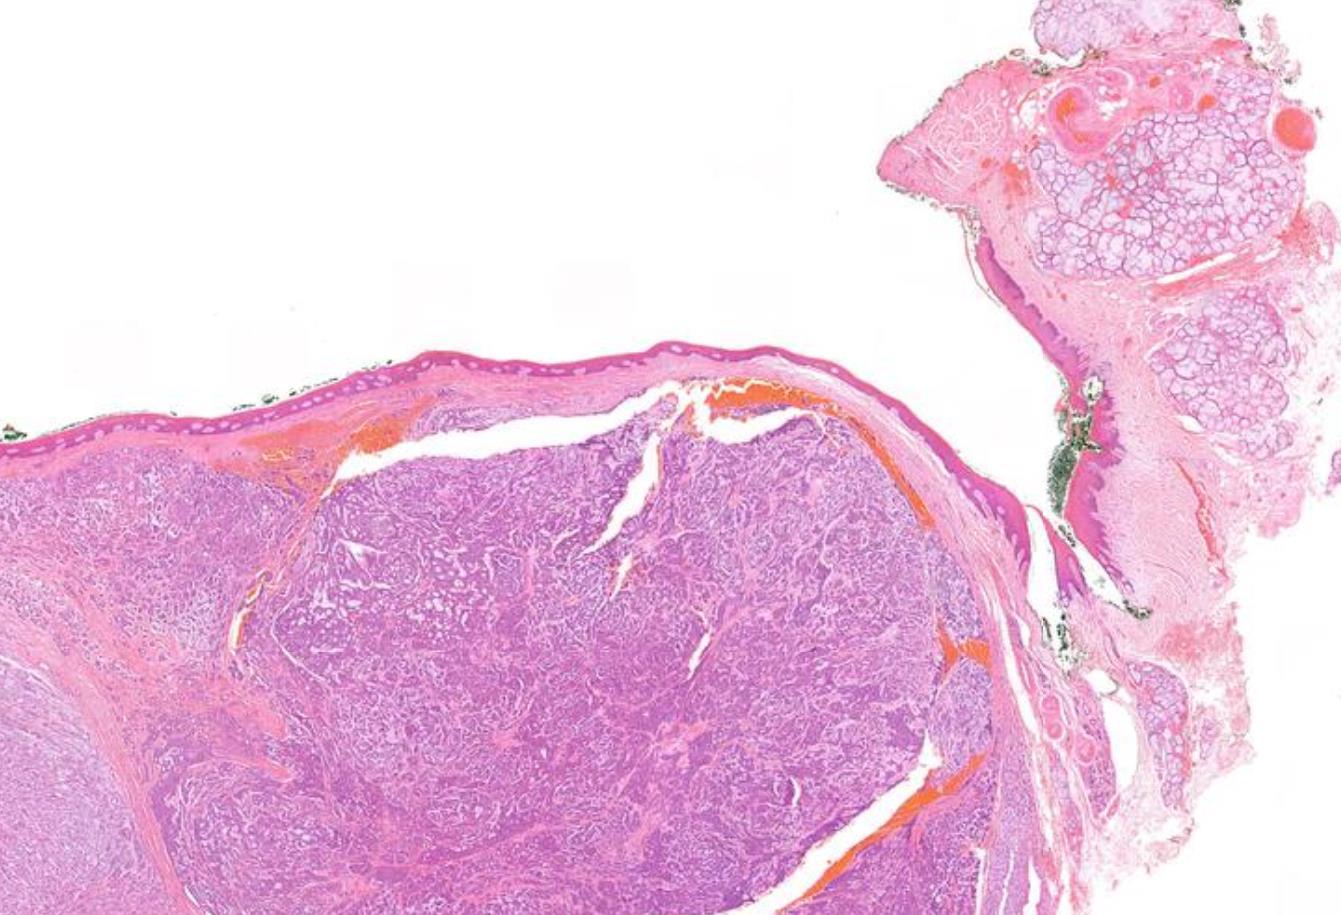

• Nodular mucosa with circumscribed tumour with infiltrative periphery • Large cells with eosinophilic granular cytoplasm • Is surface epithelium normal?

Case 4- Salient points

Granular cell tumour